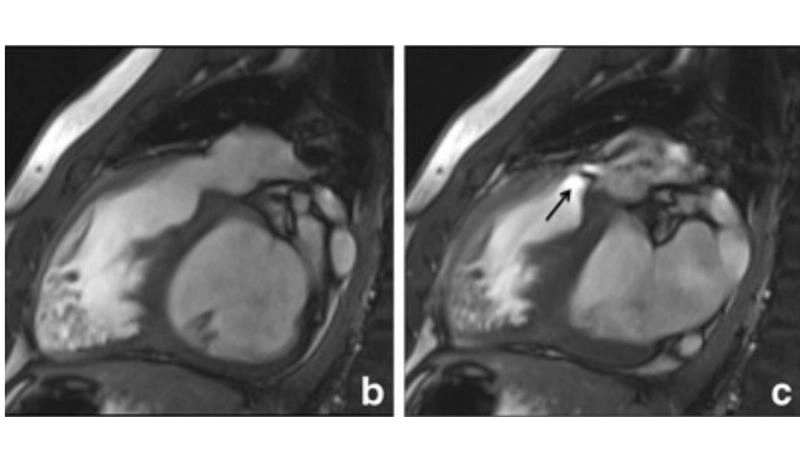

Images visual examples of pulmonary regurgitation (insufficiency)

Medical images often show backward blood flow on echocardiography, highlighting the valve’s structural damage. Such visuals help patients and physicians understand the severity of the condition and guide treatment decisions effectively.